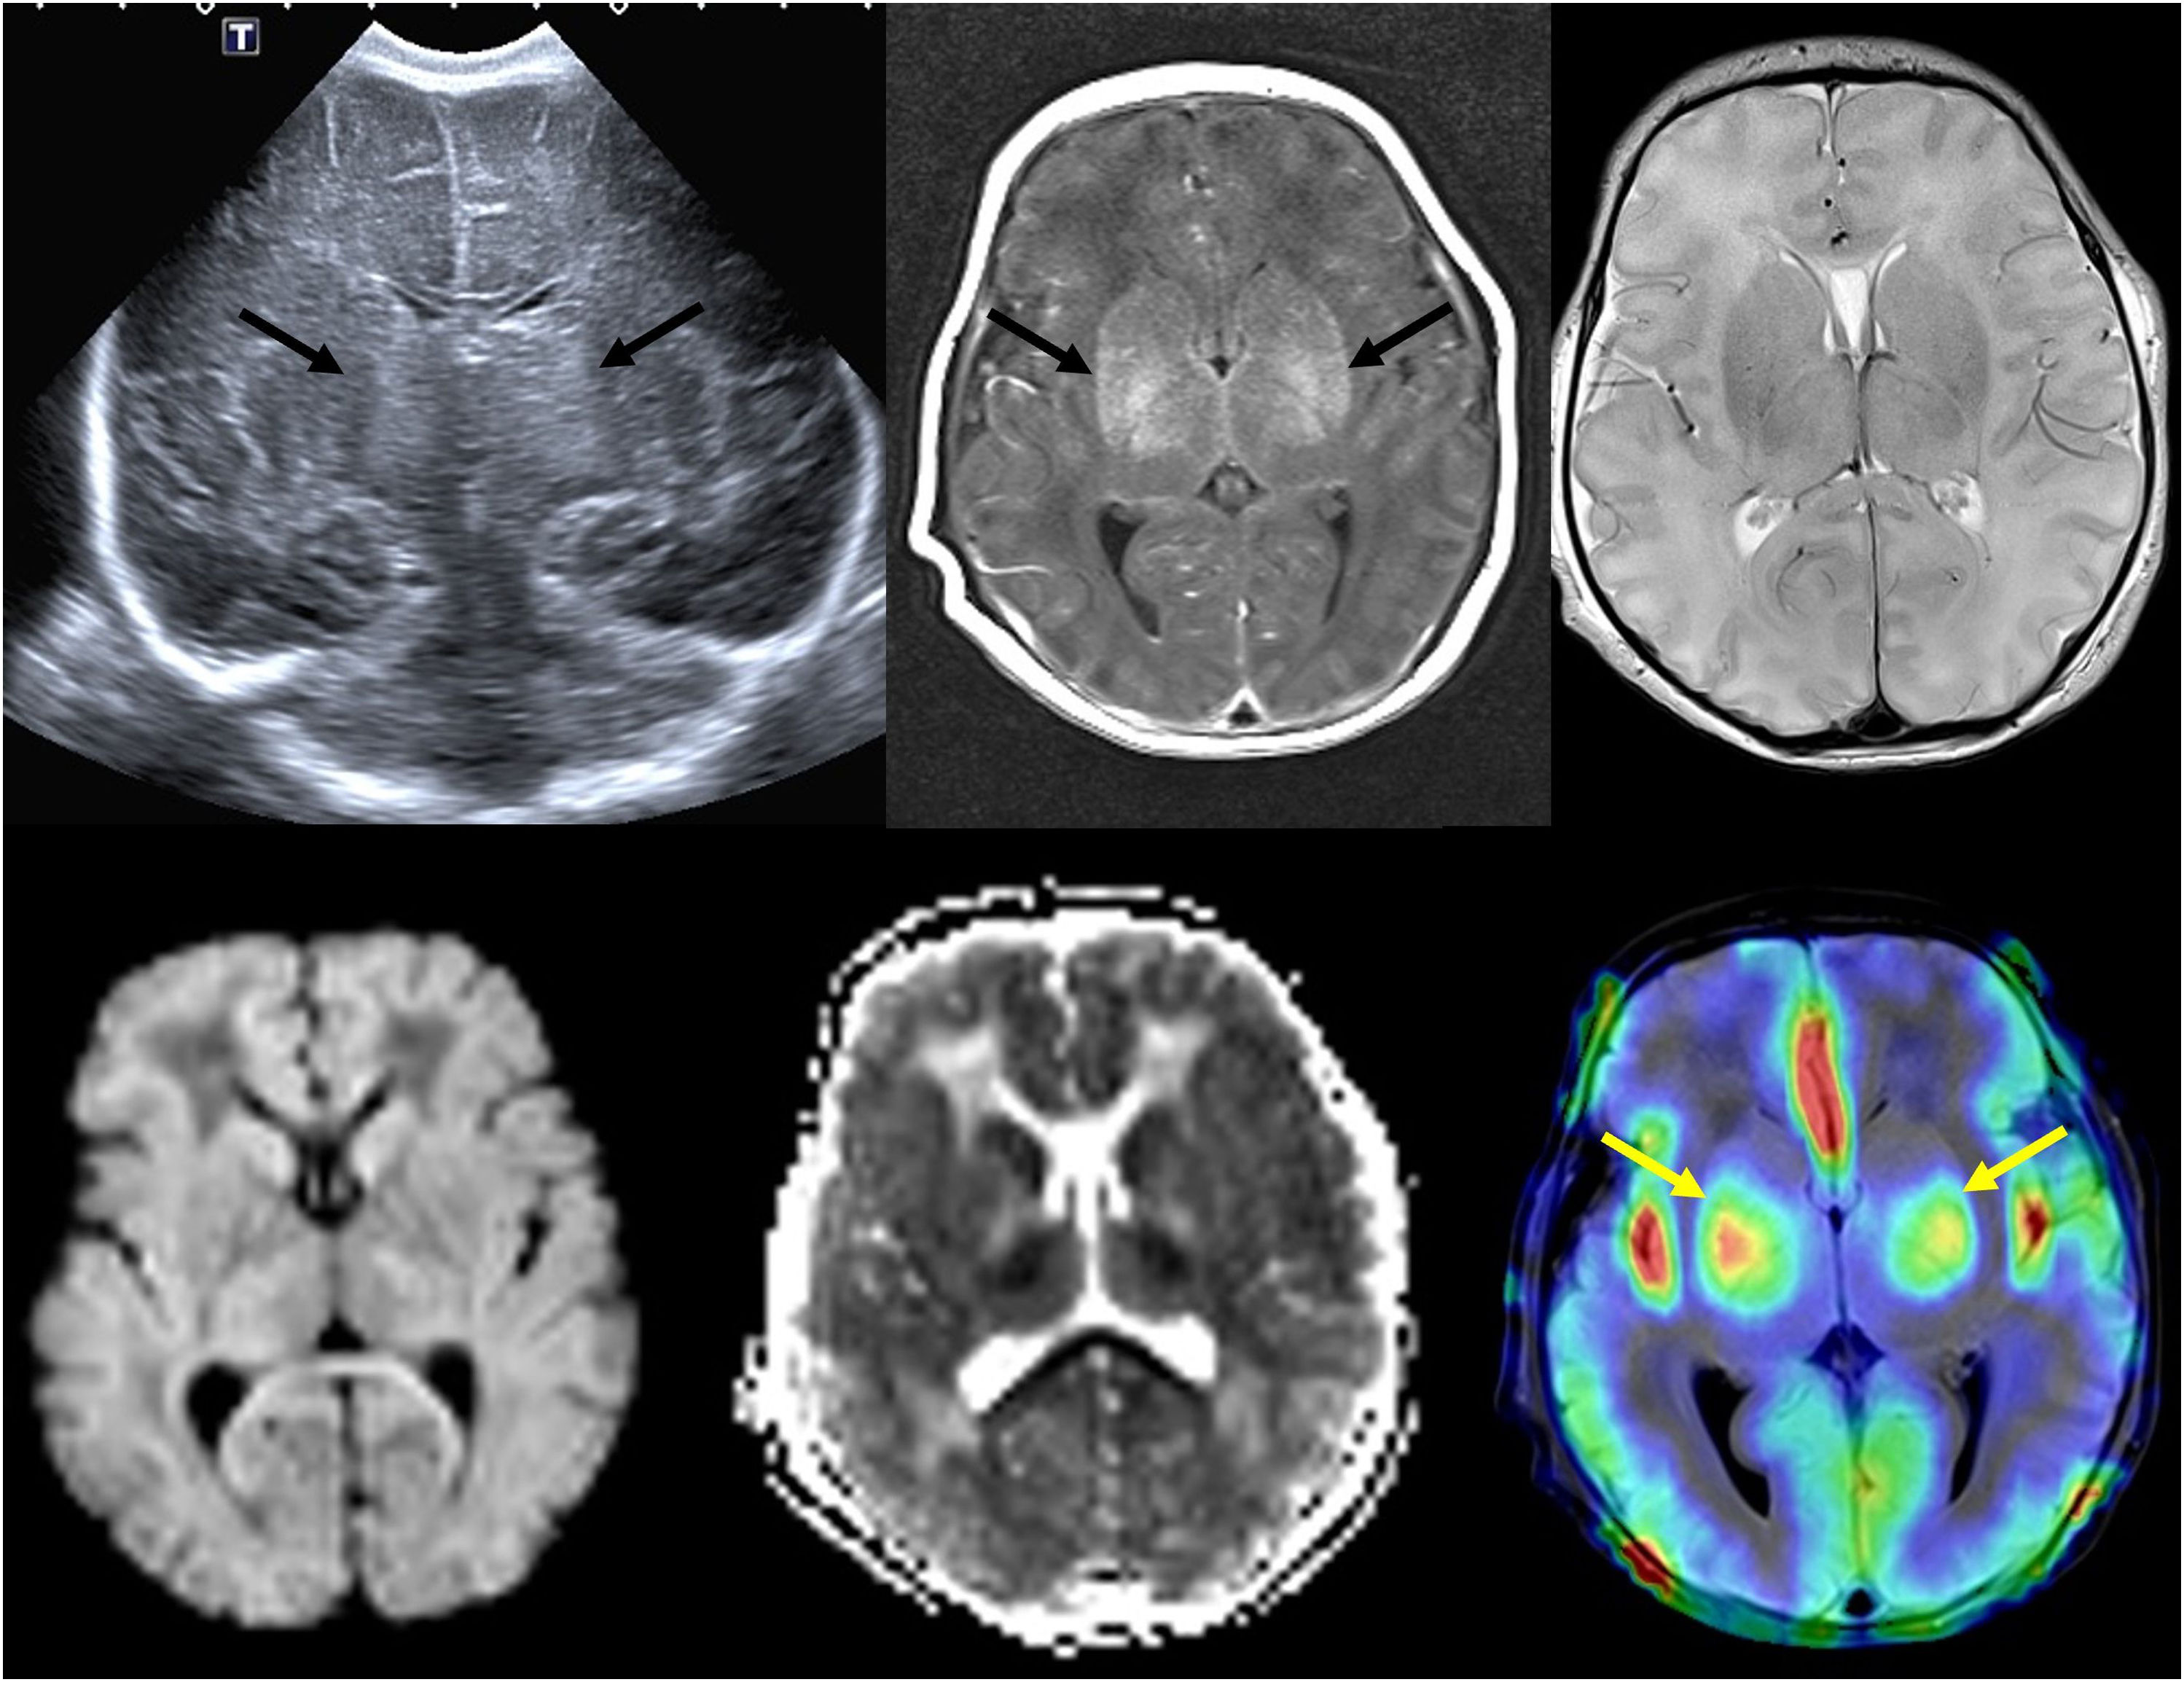

Advances in computed tomographyNovel computed tomography (CT) techniques include dual-energy and photon-counting systems with enhanced image quality and lower radiation doses. Dual-energy CT scanners can generate virtual unenhanced images that allow visualization of kidney stones or iodine maps that can be useful for visualization of lung perfusion in cases of pulmonary embolism. Photon-counting CT (PCCT) scanners generate higher-quality images with lower radiation and contrast doses. It is estimated that PCCT could reduce radiation doses by approximately 30%–60%, depending on the imaging protocol and clinical question.2 These advances allow mapping and quantification of iodine uptake, achieving more accurate tissue differentiation, enhanced material decomposition and improved three-dimensional reconstruction of tumors and 3D printing, facilitating planning of complex surgeries and integration of imaging and surgical robotics, and therefore contributing to advances in image-guided surgery (Fig. 1).